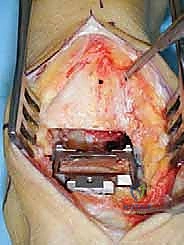

1. الشق الجراحي والوصول للمفصل

يقوم الجراح بإجراء شق أمامي طولي (Anterior Approach) في منتصف الكاحل. يتم إبعاد الأوتار والأوعية الدموية والأعصاب بعناية فائقة (هنا تتجلى أهمية مهارات الجراحة الدقيقة التي يمتلكها الدكتور هطيف) للوصول إلى محفظة المفصل.